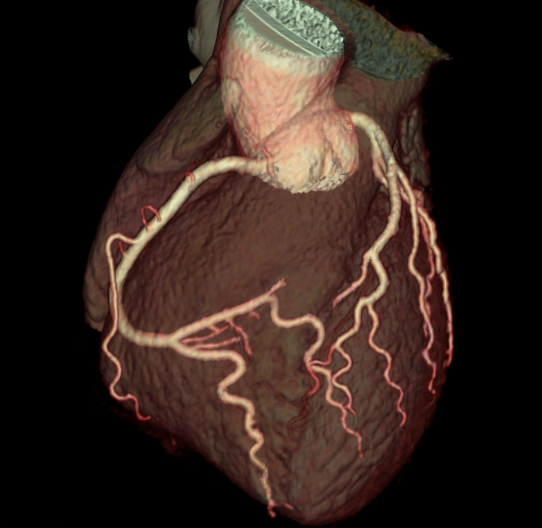

Διεξάγεται σε αξονικό τομογράφο πολλαπλών τομών (>128 detectors) με εξειδικευμένο λογισμικό απεικόνισης και επεξεργασίας των δεδομένων της παλλόμενης καρδιάς. Με την χρήση ακτίνων Χ, υπό ηλεκτροκαρδιογραφικό συντονισμό, διεξάγεται λήψη εγκάρσιων τομών της καρδιάς και με ειδική επεξεργασία δημιουργείται τρισδιάστατη εικόνα του καρδιακού μυ, των καρδιακών βαλβίδων και των στεφανιαίων αγγείων. Στον εξεταζόμενο χορηγείται σκιαγραφική ουσία που δίνει την δυνατότητα ανάδειξης στένωσης ή άλλων ανωμαλιών στις αρτηρίες.

Ακρογωνιαίος λίθος της διαγνωστικής αξίας της αξονικής στεφανιογραφίας είναι η δυνατότητα χαρακτηρισμού των αθηρωματικών πλακών (επασβεστωμένες, μικτής σύστασης, μη-επασβεστωμένες) ανάλογα με το ποσοστό εναπόθεσης ασβεστίου σε αυτές που καθοδηγεί την μετέπειτα κλινική απόφαση και θεραπεία.

Αυξανόμενα στοιχεία αναδεικνύουν τόσο την διαγνωστική επάρκεια όσο και την υπεροχή της αξονικής στεφανιογραφίας έναντι άλλων παραδοσιακών μεθόδων απεικόνισης της καρδιάς. Το σημαντικότερο πλεονέκτημα είναι η αναίμακτη διαδικασία δίχως ουσιαστική επικινδυνότητα και η δυνατότητα επαναληπτικών εξετάσεων προς σύγκριση και εποπτεία της πορείας της στεφανιαίας νόσου προ και μετά θεραπευτικής αγωγής.